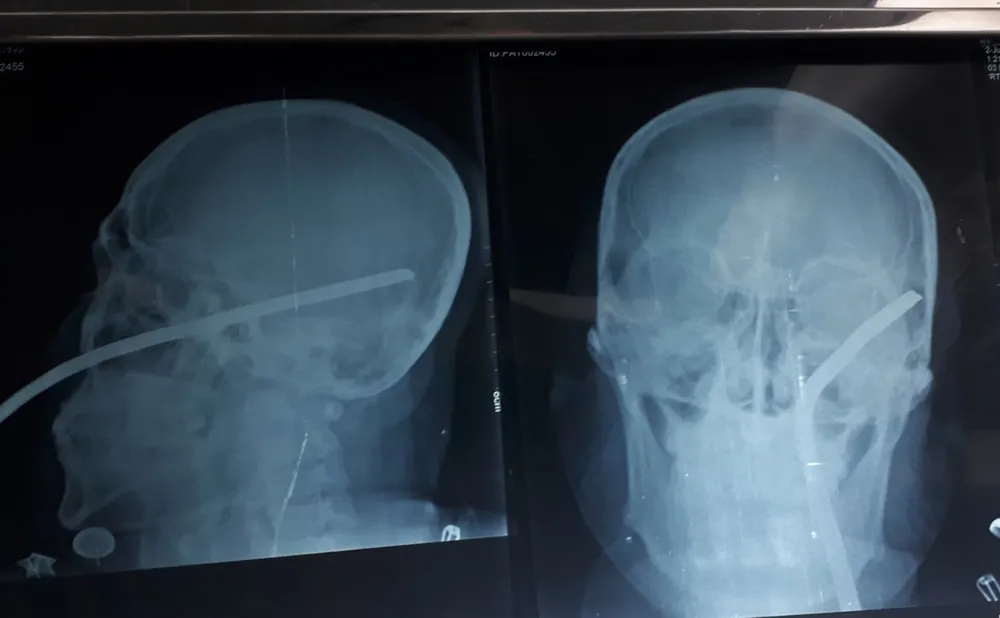

Trước đó, ngày 22-7, trong lúc đang làm nhiệm vụ trên tuyến đường tỉnh 831, ông Nguyễn Minh V., Trưởng Công an xã Tuyên Bình, huyện Vĩnh Hưng, tỉnh Long An bị một thanh sắt bay cắm vào mặt, đâm xuyên đầu, làm nạn nhân bất tỉnh.

Sau khi sự việc xảy ra, nạn nhân được đưa đến Bệnh viện Chợ Rẫy TPHCM cấp cứu. Bác sĩ đã phẫu thuật lấy thanh sắt ra. Sau 8 ngày điều trị tại Bệnh viện Chợ Rẫy, sức khỏe nạn nhân đã dần hồi phục, tự đi đứng, ăn uống, sinh hoạt bình thường.